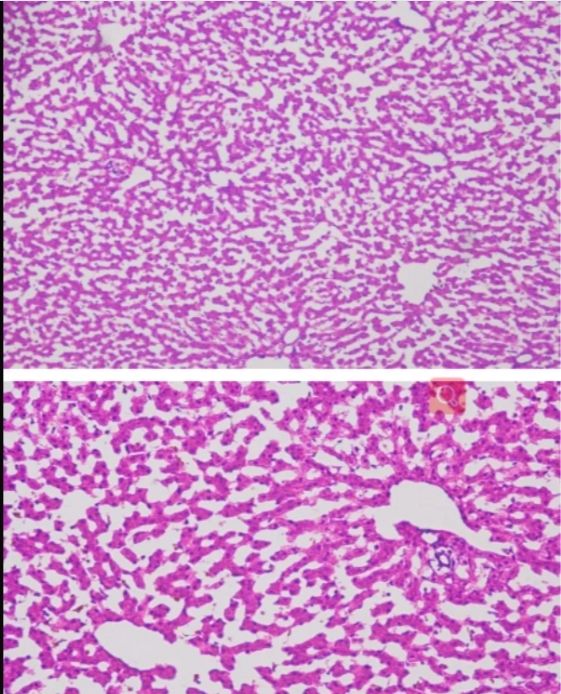

小鼠大腦冰凍切片

冰凍切片

此外,在染色性能方面,兩種切片技術(shù)也各有千秋。石蠟切片適用于多種染色技術(shù),如H&E染色等,能夠清晰地展示組織的細(xì)胞結(jié)構(gòu)和形態(tài)。而冰凍切片則更多地應(yīng)用于免疫組化和原位雜交等特殊染色技術(shù),為科研人員提供了更多維度的觀察手段。